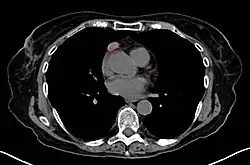

• CT scan

• Thymoma typically presents in the anterior/superior mediastinum